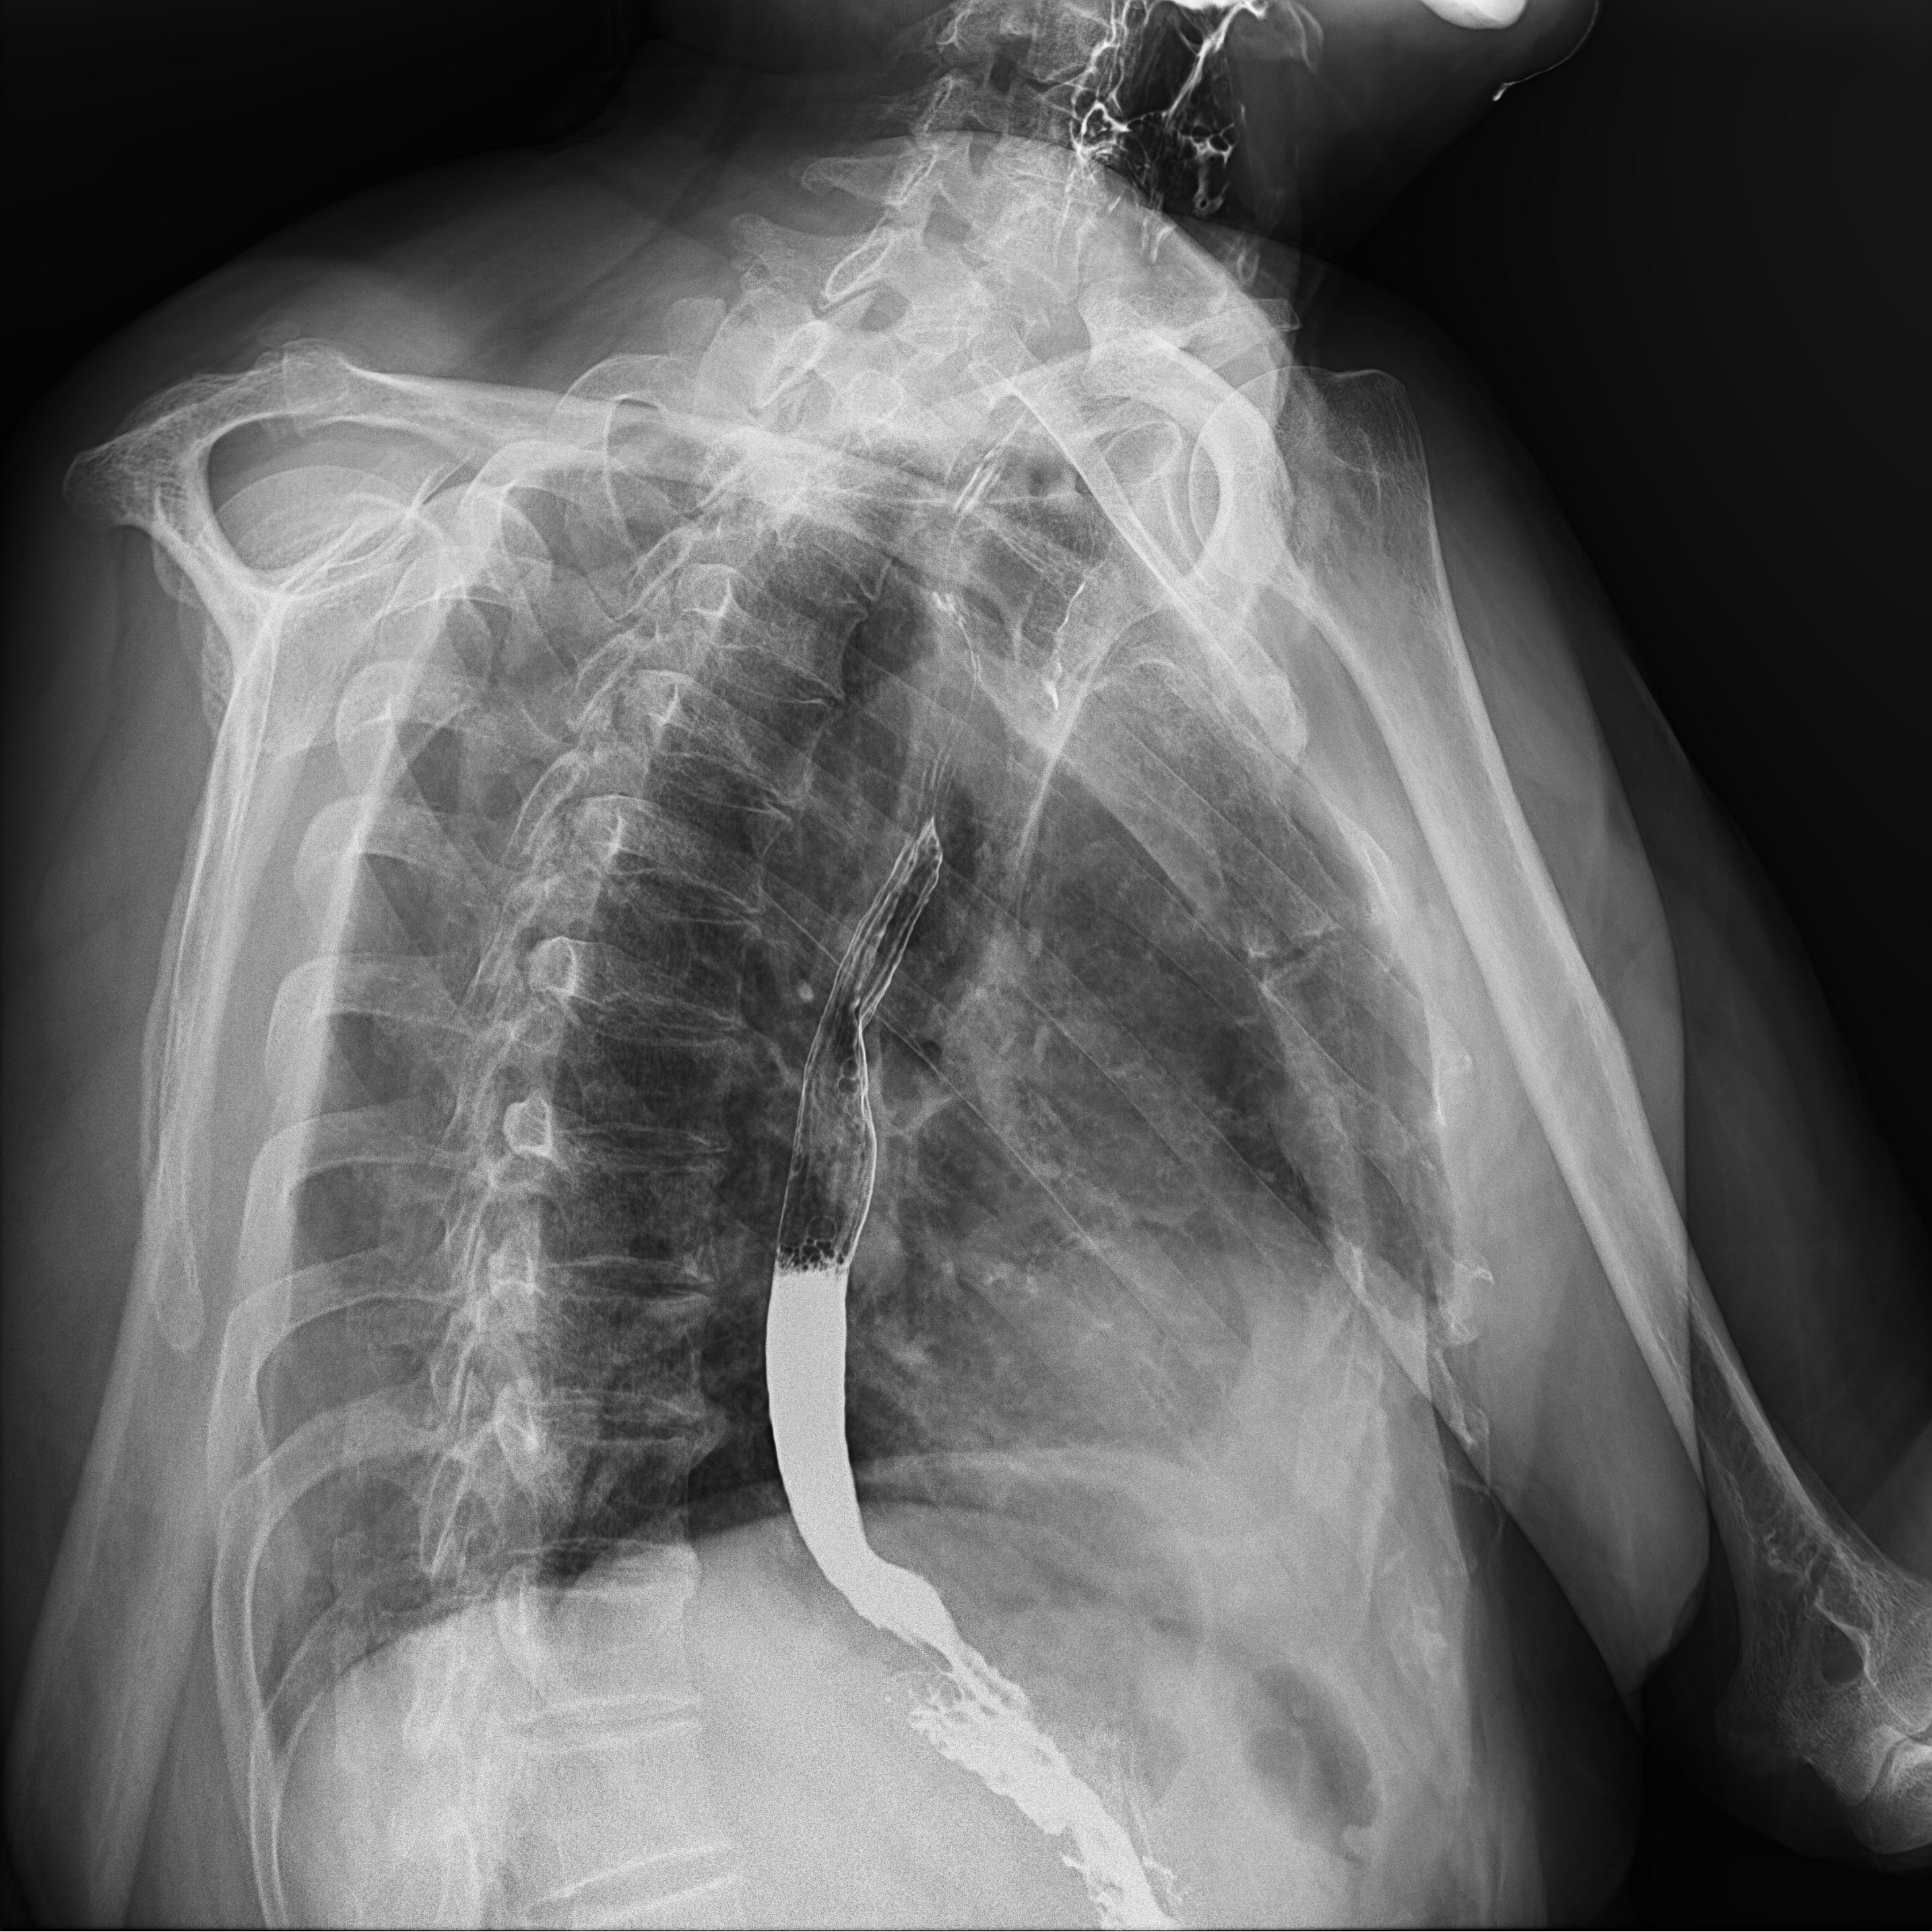

頸部片子